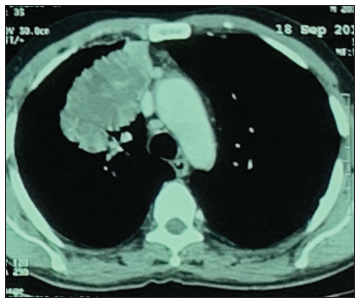

During his hospitalization, he had a small hemoptysis. A chest CAT showed a mass in the right pulmonary lobe (Figure 2), whose fine needle aspiration was compatible with adenocarcinoma.